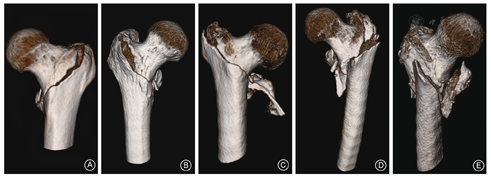

目前,多层螺旋CT及三维重建技术已普遍应用于骨与关节创伤的诊断。基于多排螺旋CT技术的容积重建法(volume rendering,VR)、多平面重组成像模式(multiplanar reconstruction,MPR)、表面遮盖重建法(surface shaded display,SSD)等成像技术已呈现出多元化发展趋势[8]。基于DICOM国际标准数据构建的先进数字骨科技术,通过重建CT检查的原始数据而输出带比例尺的高精度、结构丰富的股骨近端三维图像及多重伪彩渲染的MPR图像,并在术前进行自由视角观察与操作,包括自由分割、自由选择剖面、二维、三维联动显示、实时交互、旋转、平移、缩放等,可保存任意观察角度。该方法可实现股骨颈干角、股骨头颈中轴线长度、股骨干内外径的精确三维测量,弥补了传统影像学评估的不足。因此,智能化的数字骨科技术将明显提高临床医生对股骨转子间骨折损伤细节的全方位把握,利于术前设计的制定,方便临床医生及时总结临床经验,从而提高临床疗效(图2)。

骨折分型是分析、描述骨折损伤规律的重要方法,常用于指导治疗及判断预后。骨折分型亦已成为临床医生之间交流、总结临床经验的标准化专业术语。过去,股骨转子间骨折分型源自常规影像学检查资料,但由于X线摄片角度选择的不确定性或二维输出的三维重建图像视角的差异性而导致了部分学术争论的出现。理论上,若想有效比较不同治疗方案的优劣势,必须严格建立在针对同一类型损伤的基础上。因此,基于数字化技术的术前自由视角的三维图像观察对确定股骨转子间骨折的临床分型尤为重要。